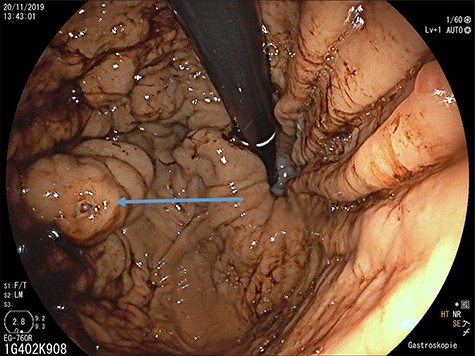

Upper gastrointestinal endoscopy: gastric varices (arrow) in the fundus after previous bleeding.

A 65-year-old man with recurrent upper gastrointestinal bleeding was admitted to the Department of Internal Medicine in our institution to identify the source of the varices and therapy. The patient had two episodes of acute upper gastrointestinal bleeding within 1 year, which was treated by sclerosing of gastric varices in a primary hospital. An important note in his medical history was a splenectomy 6 decades before after splenic rupture by blunt abdominal trauma. Endoscopy of the upper gastrointestinal tract showed isolated gastric fundus varices with the absence of oesophageal varices (Fig. 1). To identify the source of the gastric varices, an enhanced computed tomography (CT) of the abdomen was performed and surprisingly demonstrated an 8 cm in diameter mass, mimicking an accessory spleen which